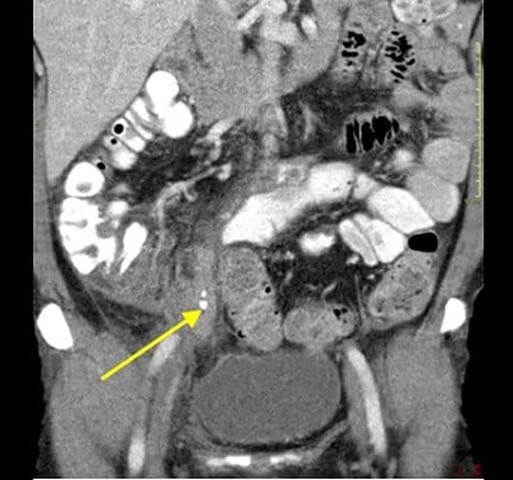

A

Enlarged appendix with an appendicolith (yellow arrow)